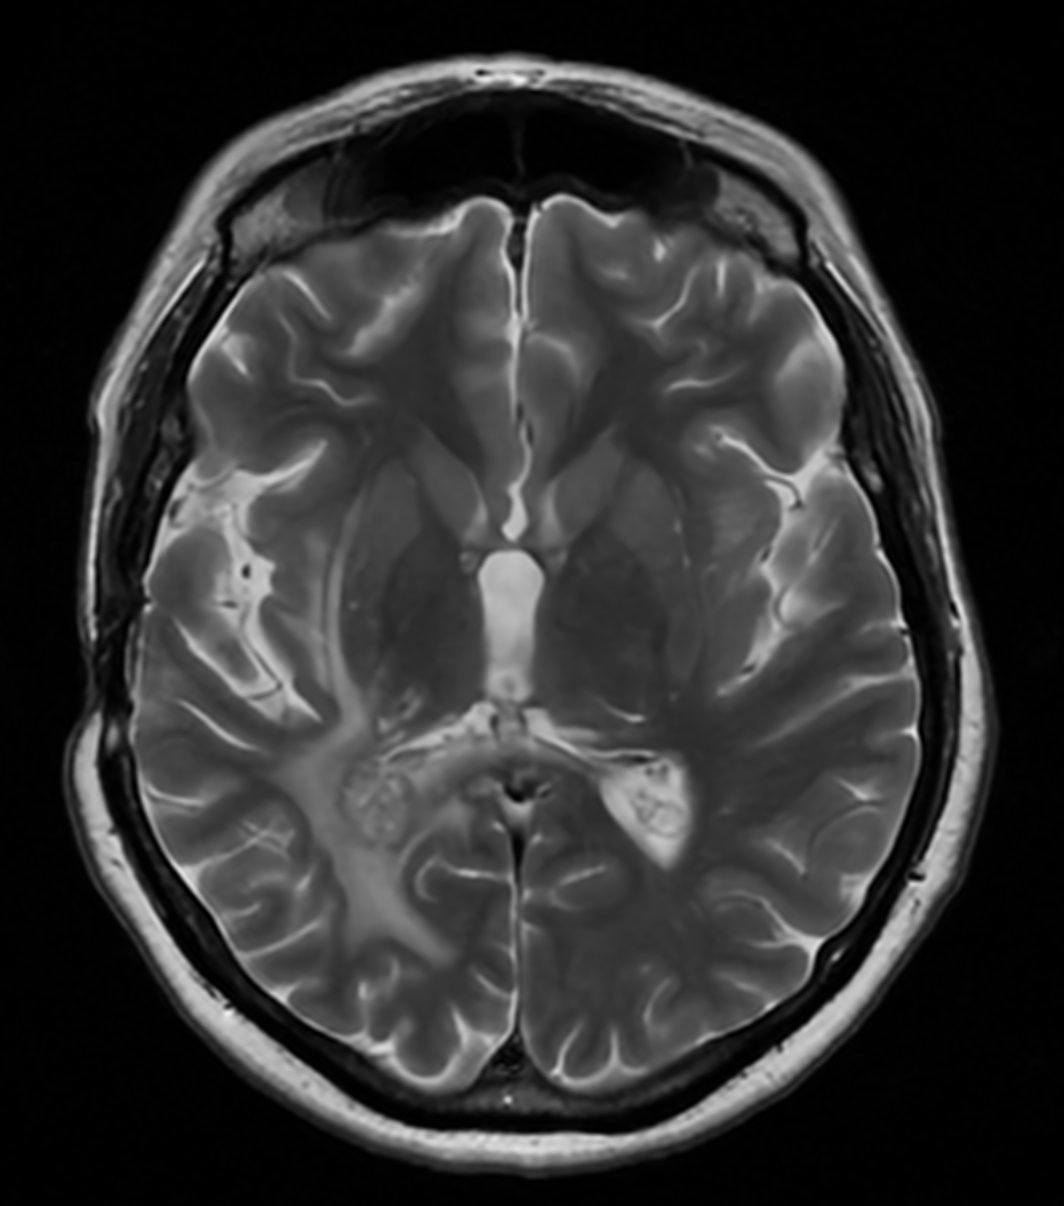

Vă prezentăm cazul unui pacient diagnosticat cu meningiom de aripă de sfenoid dreaptă, o tumoră cerebrală benignă care se dezvoltă...